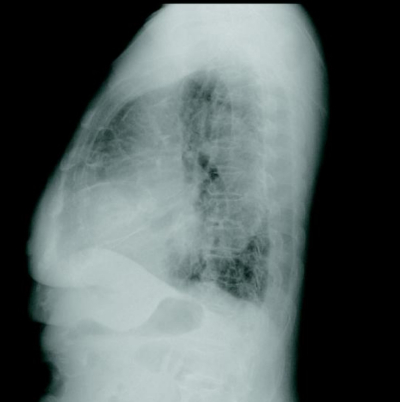

検査所見 : 尿所見:蛋白:(-)、糖:(-)、ケトン体:(-)、潜血:(-)。血液所見:赤血球 444 万、Hb 13.5 g/dL、Ht 41 %、白血球 6,900(好中球 65 %、好酸球2%、好塩基球0%、単球4%、リンパ球 29 %)、血小板 22 万。血液生化学所見:総ビリルビン 0.5 mg/dL、AST 21 U/L、ALT 18 U/L、LD 175 U/L(基準 120〜245)、ALP 166 U/L(基準 115〜359)、γ-GTP 35 U/L(基準8〜50)、CK 121 U/L、尿素窒素 20 mg/dL、クレアチニン 0.7 mg/dL、血糖 103 mg/dL、Na 142 mEq/L、K 3.9 mEq/L、Cl 101 mEq/L。脳性ナトリウム利尿ペプチド(BNP)2,200 pg/mL(基準 18.4 以下)。心電図及び胸部エックス線写真を別に示す。